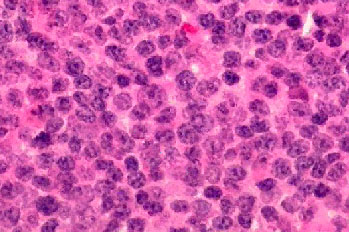

Histology of the conjunctival biopsy.